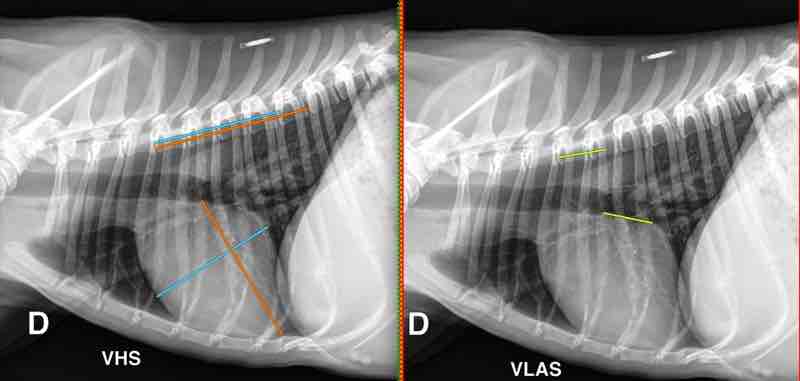

Figure 1

Figure 2